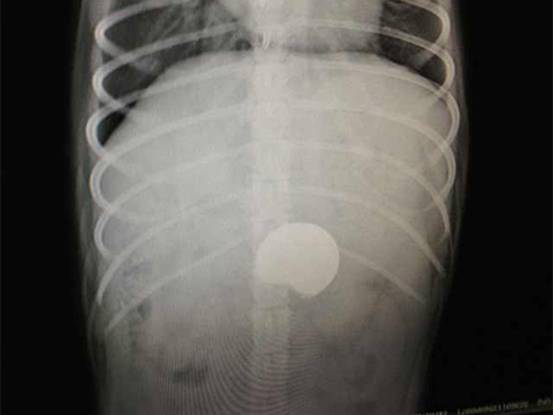

主诉:该犬自小有咬食杂物的恶习,3天前啃咬一枚硬币后不慎整个吞下,一直未见排出且精神日渐沉郁,食欲废绝并伴随不时呕吐。呕吐物为黄色透明状胃液。医生根据主人提供的信息排除传染病的可能性,立即着手拍摄X光片,DR显示该犬胃内有高密度异物。考虑到长时间呕吐情况,自行排出异物的可能性不大,医生切合实际与主人商议,该犬主人同意实施胃切开手术。

图3:DR诊断正位照